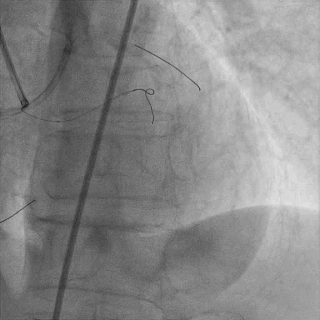

微导管交换工作导丝至D2#远端

双腔微导管辅助下,导丝在逆向造影指引下成功通过LAD闭塞段,逆向造影显示导丝走行于LAD真腔内

交换工作导丝至LAD远端

预扩球囊依次扩张LAD近中段病变处,造影可见远端血管显影,导丝位于真腔。

于LAD近中段植入Tivoli 2.75*33mm支架一枚,高压球囊后扩张后,血流TIMI3级